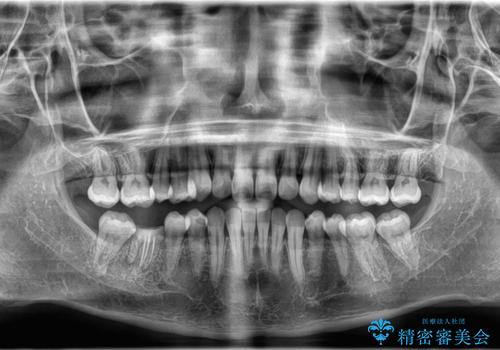

非抜歯矯正で八重歯を改善|短期間8か月で美しい歯並びに|インビザラインライト上顎のみで矯正

短期間(約8か月)の治療で歯並びが整い、患者様も大変喜ばれました。